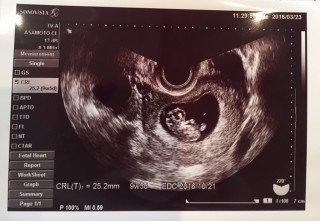

今日が1回目の妊婦健診でした。 3ヶ月前に稽留流産をしているので、心拍が確認出来てからも順調に育っているかとても心配でした。 赤ちゃんはちゃんと成長してくれていて、8週1日で16.5㎜だったのが25.2㎜に! 手足が見えて可愛い。安心出来ました(^^)